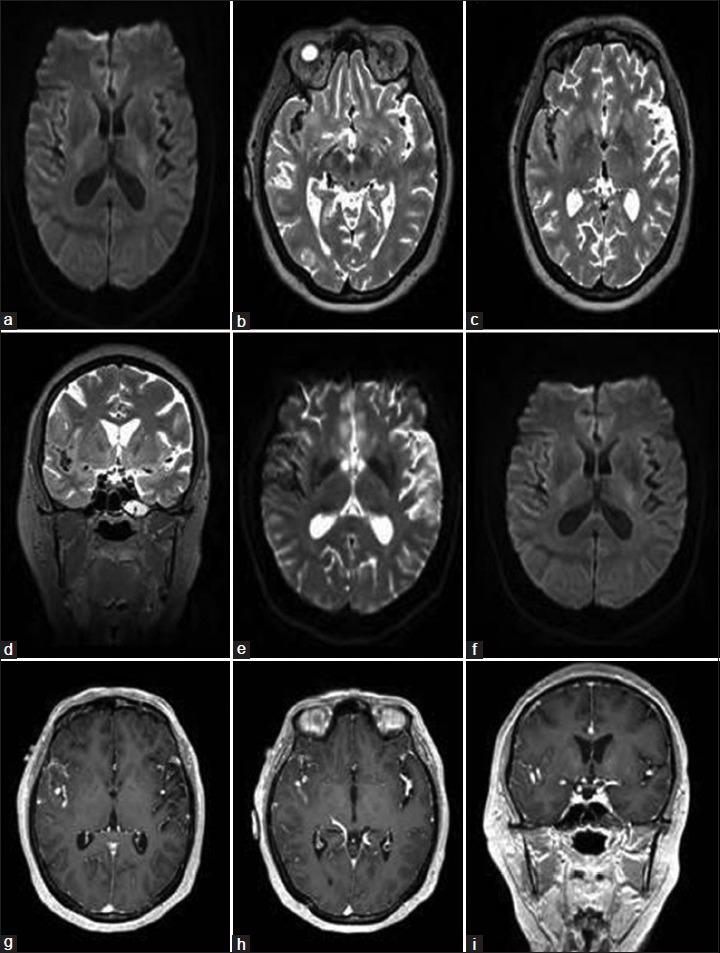

CASE DESCRIPTION

We describe the unique case of a 47-year-old female who developed multiple FIAs over a 6-year period without an obvious underlying pathology. The patient's medical history was significant for obesity, migraine headaches, insomnia, breast cancer, and chronic skin rash. Various diagnoses were explored including infectious etiologies, autoimmune vasculopathies, malignancy-related causes, connective tissue disorders, and underlying genetic conditions. However, all investigations, including aneurysm wall and skin biopsies were negative or deemed noncontributory toward making a definitive diagnosis.

病例描述

我们描述了一名47岁女性的独特病例,该患者在6年时间里出现了多个FIAs,且无明显潜在病理情况。患者的病史包括肥胖、偏头痛、失眠、乳腺癌和慢性皮疹。对各种诊断进行了探索,包括感染性病因、自身免疫性血管病变、恶性肿瘤相关病因、结缔组织疾病和潜在遗传疾病。然而,所有检查,包括动脉瘤壁和皮肤活检均为阴性或被认为对明确诊断无帮助。

结论

我们报告了一例不寻常的病例,一名患者脑血管造影正常,在6年时间里出现多个FIAs,且无明显潜在病因。鉴于目前该病的自然史尚不清楚,建议对该病例进行密切的临床和影像学随访。本文对关于多发性梭形颅内动脉瘤潜在病因的文献进行了综述。